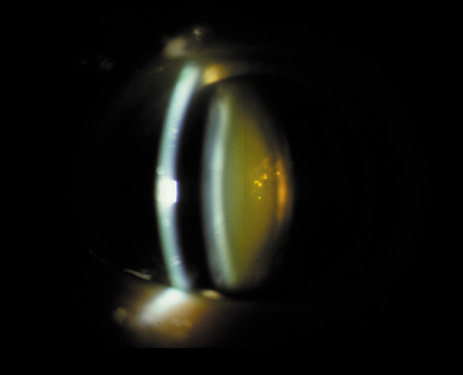

One can examine this type of cataract with direct illumination, using the narrow and broad beams of the slit-lamp to show the characteristic granular inner surface immediately in front of the posterior capsule (Fig. 13). The problem with this technique, however, is that patients may not tolerate any prolonged direct illumination because of the glare. Retroillumination is therefore more useful for revealing the outline of the opacity, since it is usually seen as an “island” in the center of the posterior capsule, which is further highlighted by the shadow cast by the opacities.33 However, in the early stages of this type of cataract, the dust-like particles that might be noticeable in the central posterior subcapsular area with direct illumination disappear or are difficult to see with retroillumination (Fig. 14). Eventually this “dusting” becomes dense enough to cast a shadow and thus appear on retroillumination. The smooth orange background of the fundus helps to highlight the rough, irregular pseudopodia-like edges of the central opacity. In advanced stages, the PSC may become a thick, calcified plaque (Fig. 15). During surgery, excessively vigorous scraping or vacuuming of the calcified opacity can lead to rupture of the posterior capsule. Usually, small remnants that are left behind after surgery are reabsorbed and do not interfere with vision; otherwise, they are easily treated with a neodymium : yttrium (Nd:YAG) aluminum garnet laser. Pathologic evidence suggests that most PSCs result from the migration of bow region cells into the potential space (along with accumulated cellular debris) between the posterior capsule and the cortex.34–36

Fig. 13. Direct slit-lamp illumination of a PSC, showing an irregular granular surface in front of the posterior capsule.